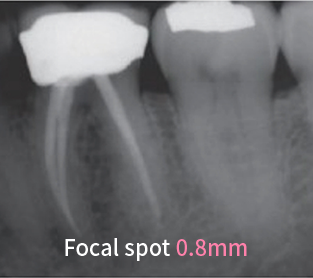

KRISTÁLYTISZTA KÉP

A 0,4 mm-es fókuszpont rendkívül éles, tiszta képet biztosít a fogorvosok számára.